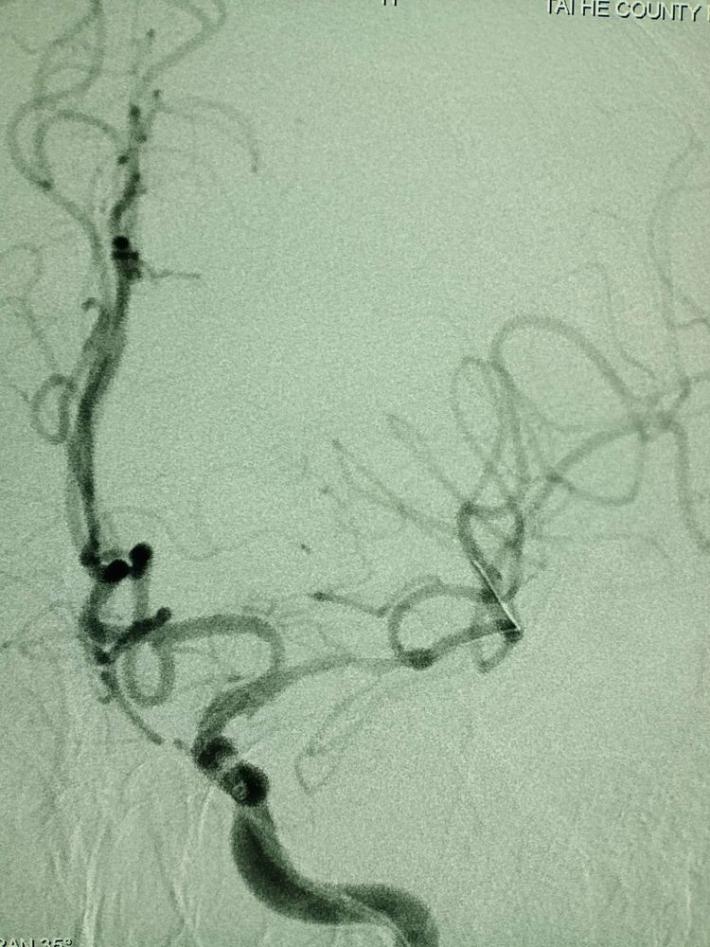

取栓后五分钟,血流减慢,难以维持,左侧大脑中动脉M1段原位狭窄。

球囊扩张

球囊扩张后30分钟,重复造影,狭窄明显改善,前向血流TICI3级。